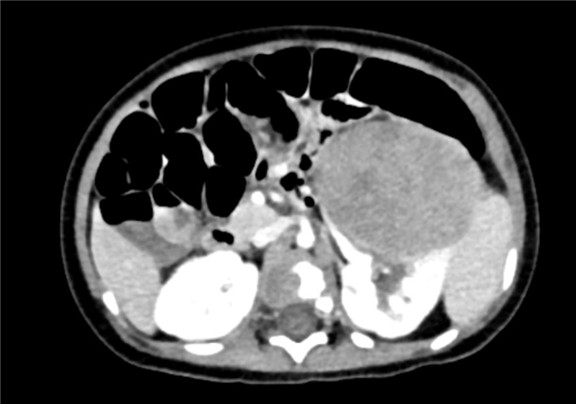

上腹部增强CT:左肾巨大占位性病变,疑似肾母细胞瘤

术前CT检查:

动脉期

静脉期

平衡期